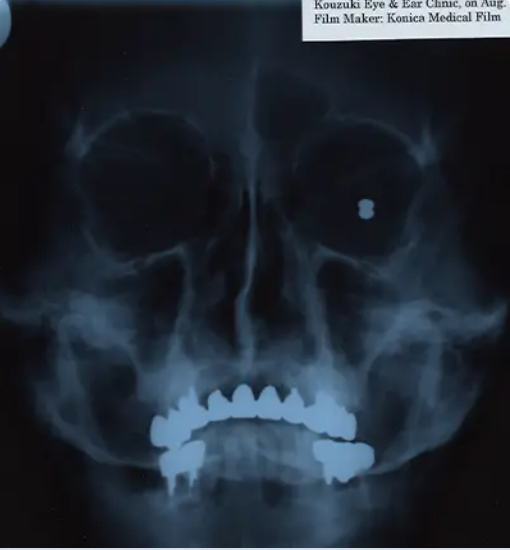

Səkkiz yaşında üzünə tüfənglə vurularaq sağ qalan Uilyam Pace başından güllə ilə yaşamaq rekorduna sahibdir. Hadisə 1917-ci ildə Texasdakı fermada baş verib. Qardaşı tüfəngin dolu olduğunu bilməyib, oynayarkən atəş açıb. Güllə Uilyamın başının arxasında qalıb, üzünü eybəcərləşdirib və bir gözündə görmə və eşitmə itkisinə səbəb olub.

Ağır xəsarətlərə baxmayaraq, adam heyrətamiz şəkildə 103 il yaşayıb. 2006-cı ildə Ginnesin Rekordlar Kitabına daxil edilib. Uilyamın həyatının bütün dövrü məhdudiyyətlərə baxmayaraq, inanılmaz idi.

O, əkinçi olub, qəbiristanlıqda baxıcı işləyib, həyat yoldaşı ilə dünyanı gəzin. İnqilabçı dərman penisilin sayəsində Uilyam gülləni çıxarmaq üçün cərrahi müdaxilədən qaçıb və bu, onu oxşar xəsarətlərdən sağ qalanlar arasında unikal edib. 2012-ci ildə o, özündən sonra inanılmaz dözümlülük və mətanətlə bağlı xatirələr buraxaraq dünyasını dəyişib.